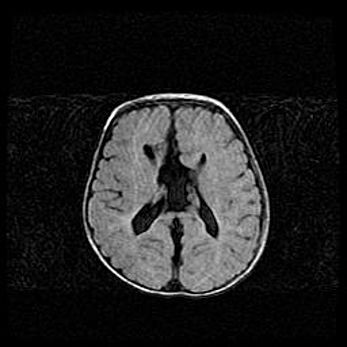

Множественные мелкие кисты перивентрикулярной области.

Киста прозрачной перегородки.

Возраст: 28 дней

Вес: 2400 г

Пол: женский

Окружность головы: 33 см

Срок гестации: 34 недели

Перивентрикулярная киста – это полостное образование в околожелудочковых областях белового вещества головного мозга. С морфологической точки зрения – это мелкоочаговая зона коагуляционного некроза, возникшая после инфаркта белого вещества. Наиболее часто поражаются начальные отделы задних рогов боковых желудочков. Обычно образования заполнены жидкостным содержимым.

Киста прозрачной перегородки может располагаться в переднем отделе межжелудочковой перегородки, в области мозолистого тела и мозжечка.